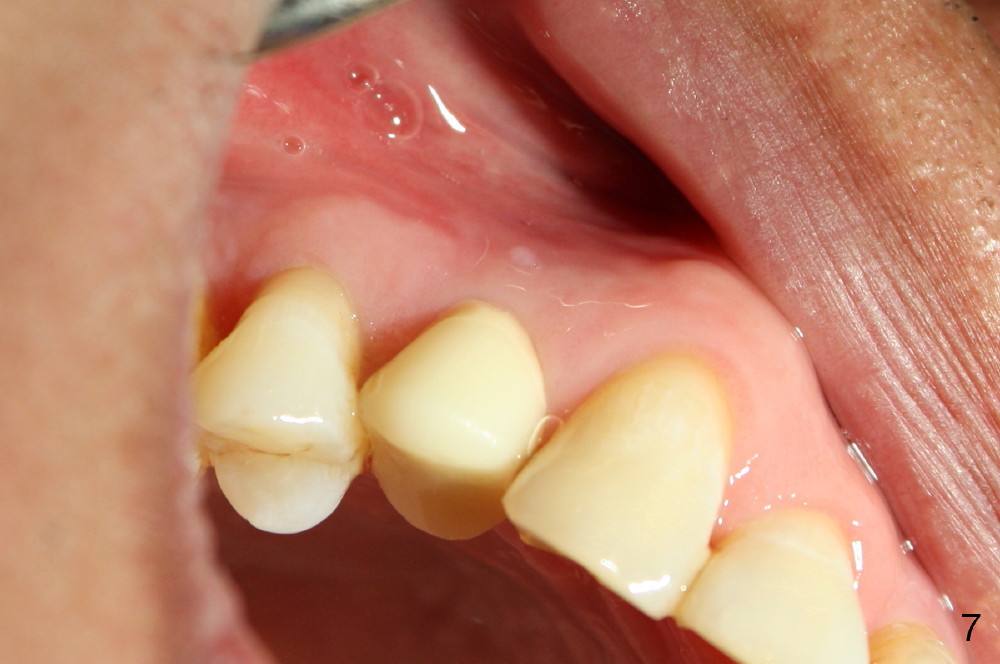

The patient returns 6 months postop for impression of a permanent restoration. The gingiva with knife-edged papillae adapts to the provisional (Fig.7). The gingiva looks healthy when the provisional is removed (Fig.8). The buccal bone resorption seems to be minimal, as compared to Fig.1,2. There is no bone loss between immediately postop (Fig.9 I; implant), 4.5 months postop (Fig.10 A: abutment), 4 and 7 months post cementation (Fig.11,12 C: crown). Soft and hard tissue morphology remains normal 7 months post cementation (Fig.13). No bone loss is observed 15 months post cementation (Fig.14). The papillae (Fig.15) and bone (Fig.16,17) remain stable 29 months post cementation.